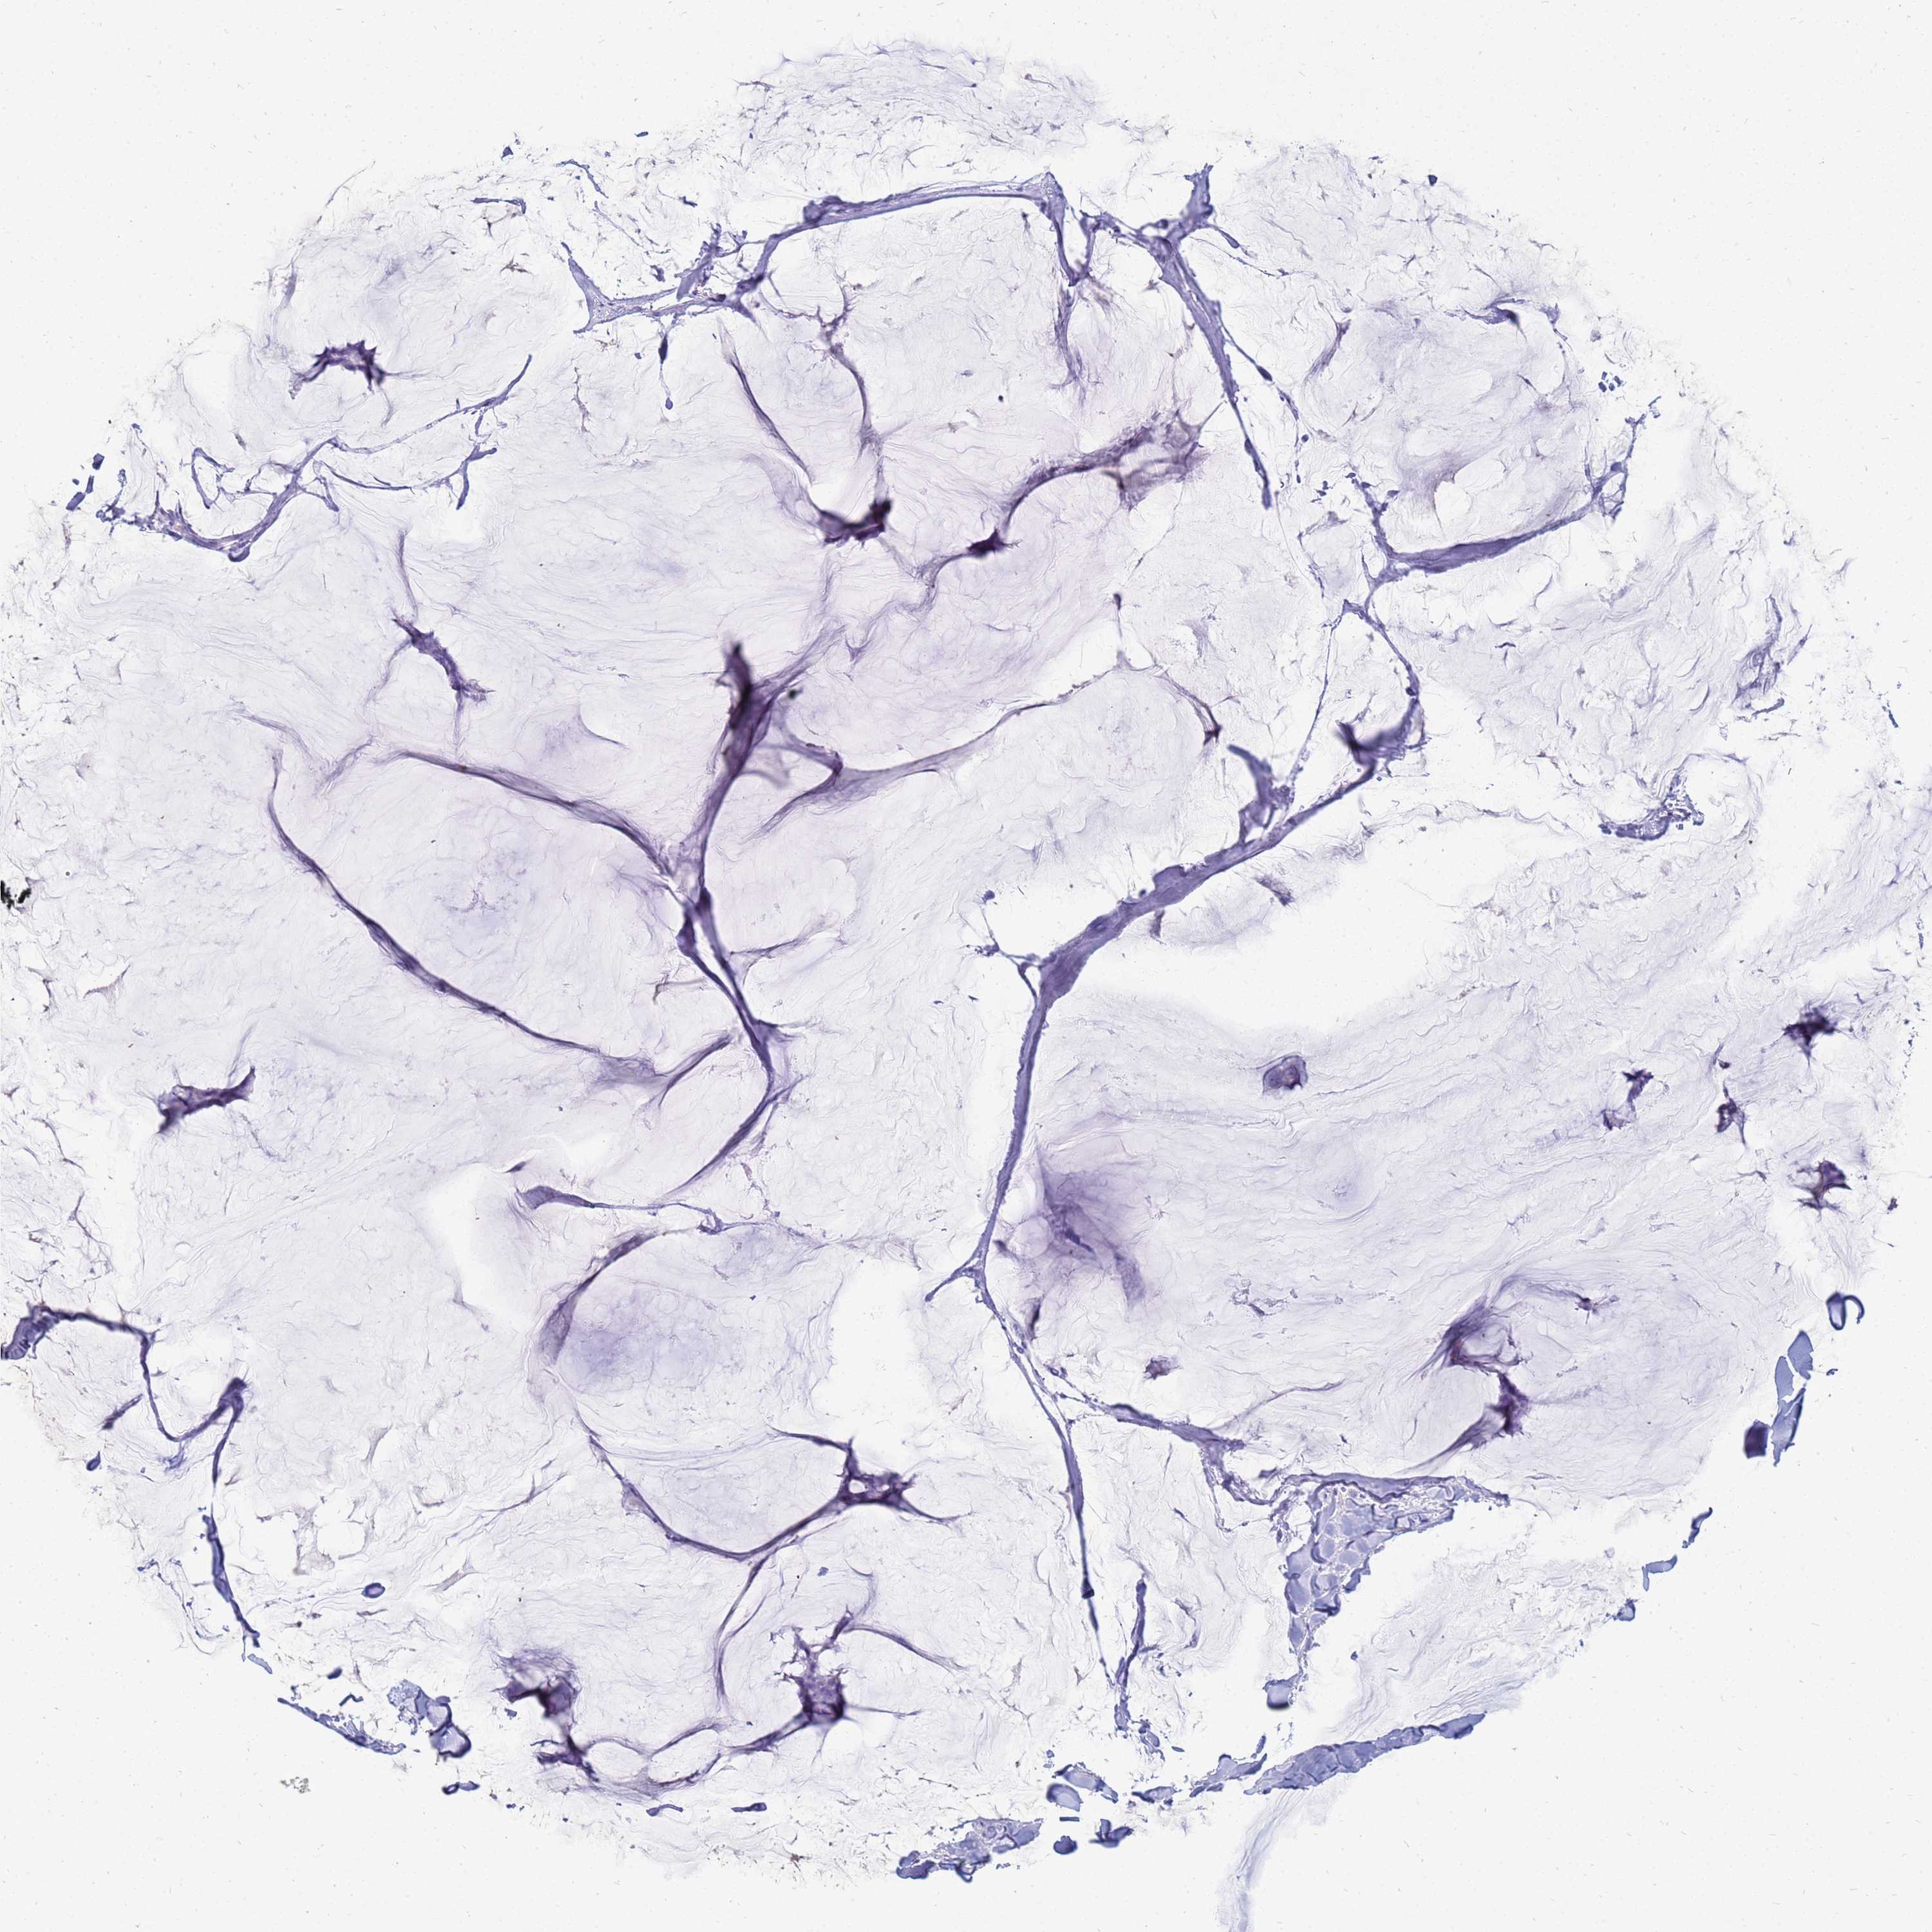

CANCER BREAST CANCER Show tissue menu

BRCA TCGA BRCA VALIDATION PROTEIN EXPRESSION